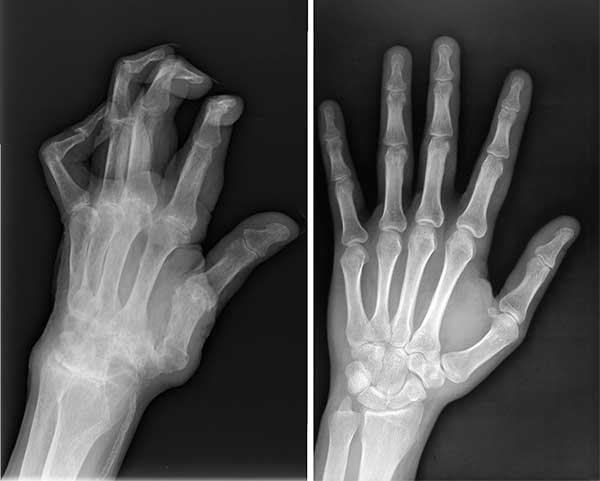

Kondisi lutut saya kala itu. Rasa sakit yang kuat

Di sana dokter melihat hasil rontgen cukup lama, kemudian menyampaikan bahwa saya tidak bisa melakukan pekerjaan fisik lagi dan mengangkat beban dengan berat lebih dari 2 kilo.

X-ray menunjukkan masalah serius dengan lutut saya

Rontgen suami sebelum dan sesudah mengonsumsi Invanil

Keadaan tangan suami saya sebelum dan sesudah mengonsumsi Invanil